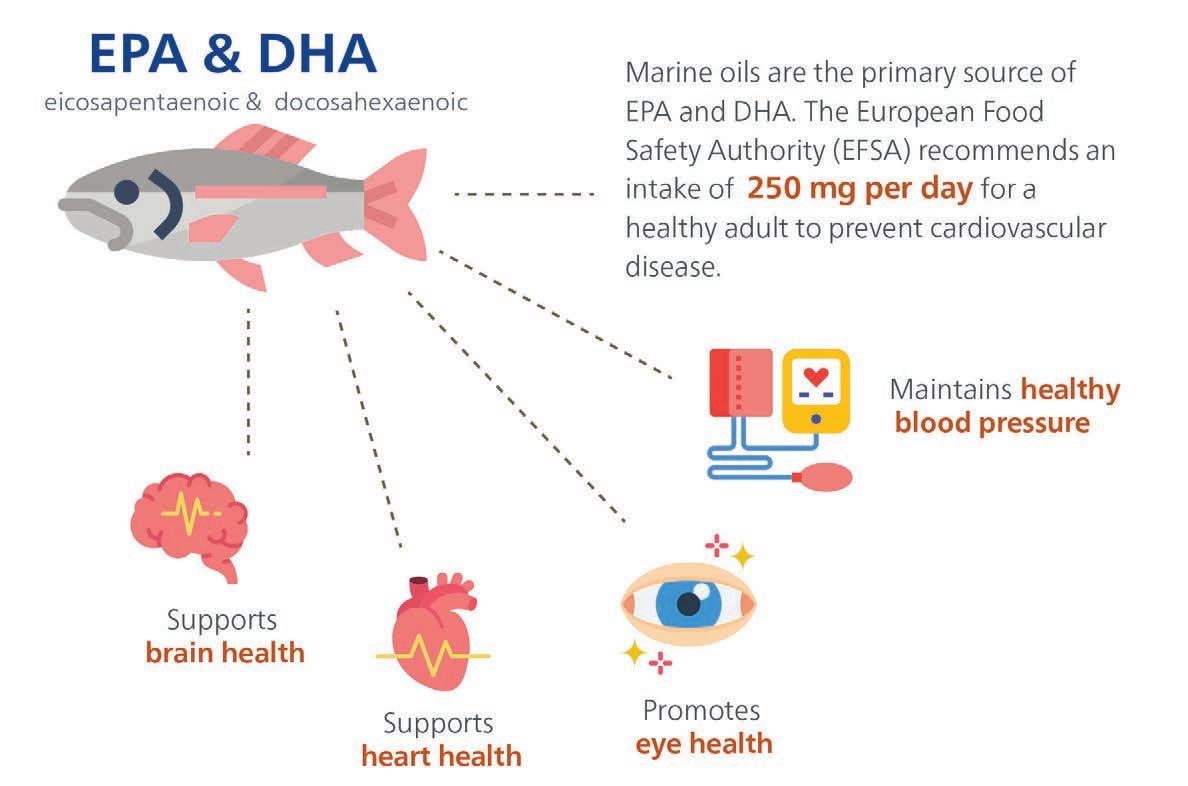

THE Nordic Council, which represents major salmon farming countries such as Norway, Iceland and the Faroe Islands, has produced a report urging people to eat more fish to help improve their health. The sixth edition of The Nordic Nutrition Recommendations is the biggest update in the report’s 40-year history.

The advice is clear when it comes to seafood: consume 300g to 450g of fish (cooked or ready to eat) each week. At least 200g should be oily fish, such as herring, mackerel and salmon.